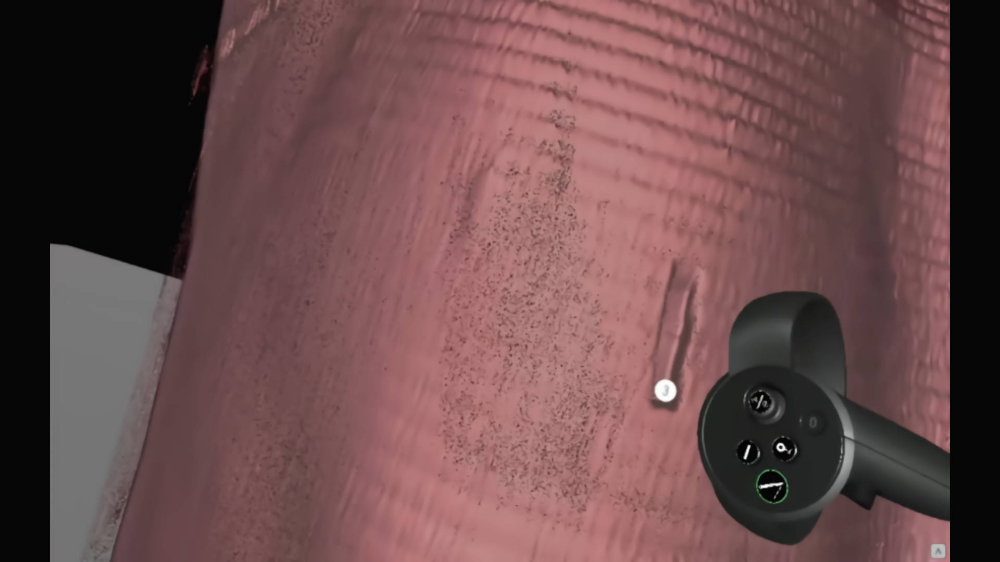

Preview of CT images from

brand new perspective

A modern program for analizing images from the tomograph

Thanks to our program, you will be able to manage lists of your patients in a quick and organized manner, saving time and more efficiently analyzing images from a computer tomograph or magnetic resonance imaging. The application allows you to load photos into the Virtual Reality environment, giving you the opportunity to view and analyze them in a new, unconventional way. Photos displayed in the form of 3D models can be freely rotated and viewed from different angles.